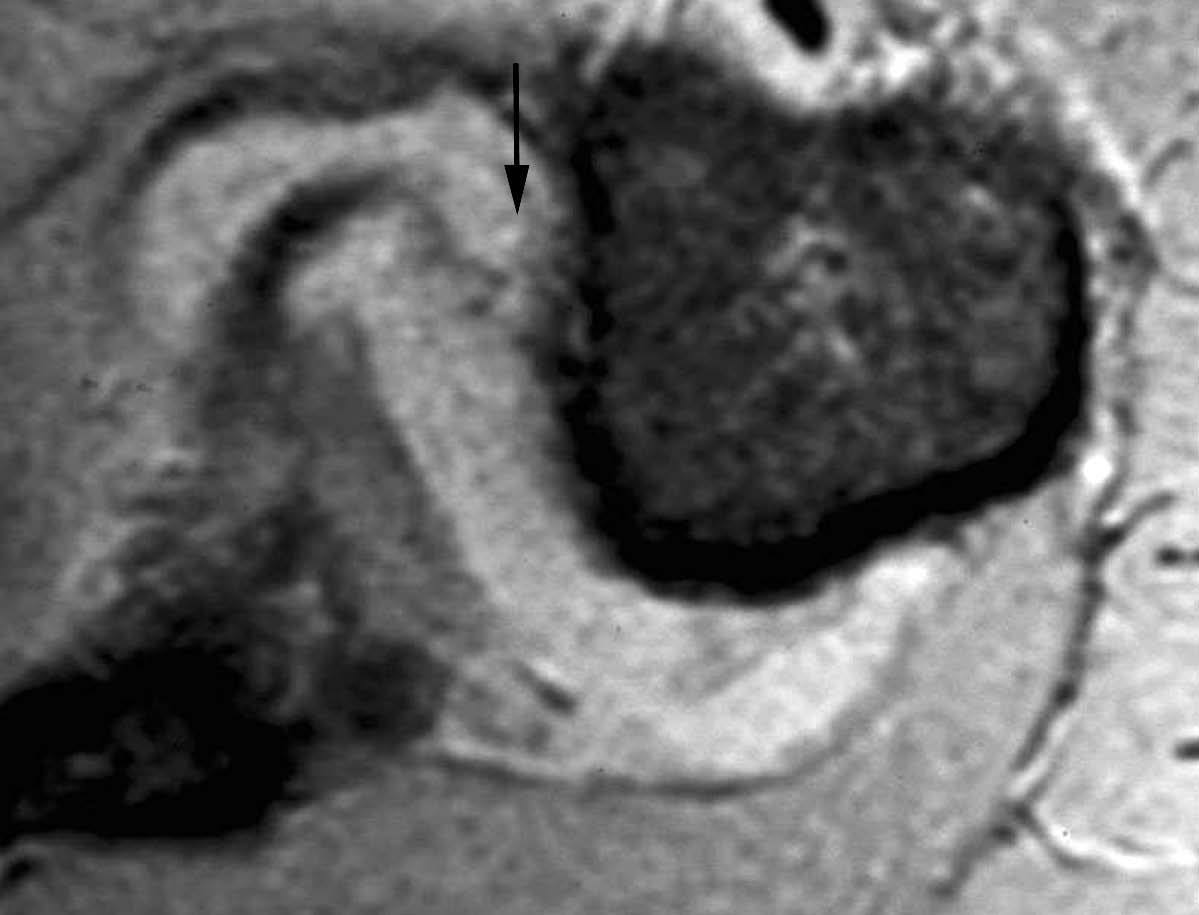

Esta lesión se produce a consecuencia de una tracción repetitiva de la unión cápsulo-perióstica posterior, produciéndose una osificación semejante a un espolón óseo (fig. 15).

Fig. 15.--Lesión de Bennett. Tomografía axial computarizada (TAC) axial (A) y resonancia magnética (RM) T1 axial (B) que revelan la presencia de un «espolón» óseo adyacente al borde glenoideo posterior (flechas en A y B). Nótese la ausencia de una lesión del labio glenoideo posterior en B.